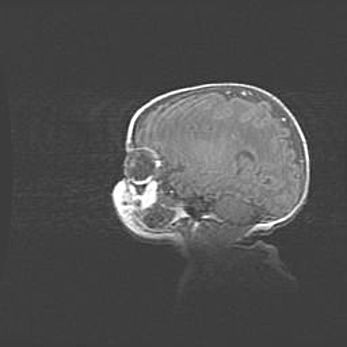

Множественные кисты обоих полушарий головного мозга, наибольшая из них в правой затылочной области. Ассиметричная атрофическая гидроцефалия.

Возраст: 7 месяцев

Вес: 5660 г

Пол: мужской

Окружность головы: 41,5 см

Срок гестации: 28-29 недель

Кисты головного мозга развиваются в результате многоочаговых некрозов вещества мозга и возникают вследствие перенесенной перинатальной инфекции, менингитов, энцефалитов, асфиксии, родовой травмы, расстройств мозгового кровообращения различного генеза. Образованию кист в веществе головного мозга плодов и новорожденных способствуют такие факторы, как высокое содержание в нем воды, недостаточная (или отсутствие) миелинизация и слабая астроглиальная реакция на повреждение.

Кисты могут сочетаться с гидроцефалией и другими поражениями головного мозга.